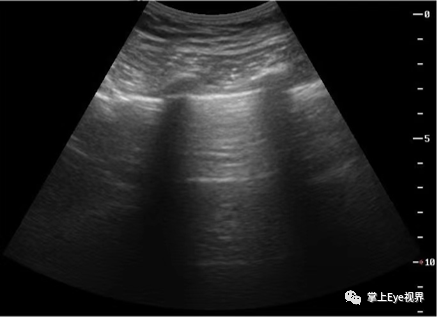

多次反射伪像

声束传播中遇到一个与换能器平行的界面,该界面两侧的声阻抗有较大差别,使之产生了很强的反射波,反射波在换能器与界面间多次反射传播,形成多段逐次畸变的重复反射图像。常见于肺、气管等部位。

图为肺的多次反射伪像